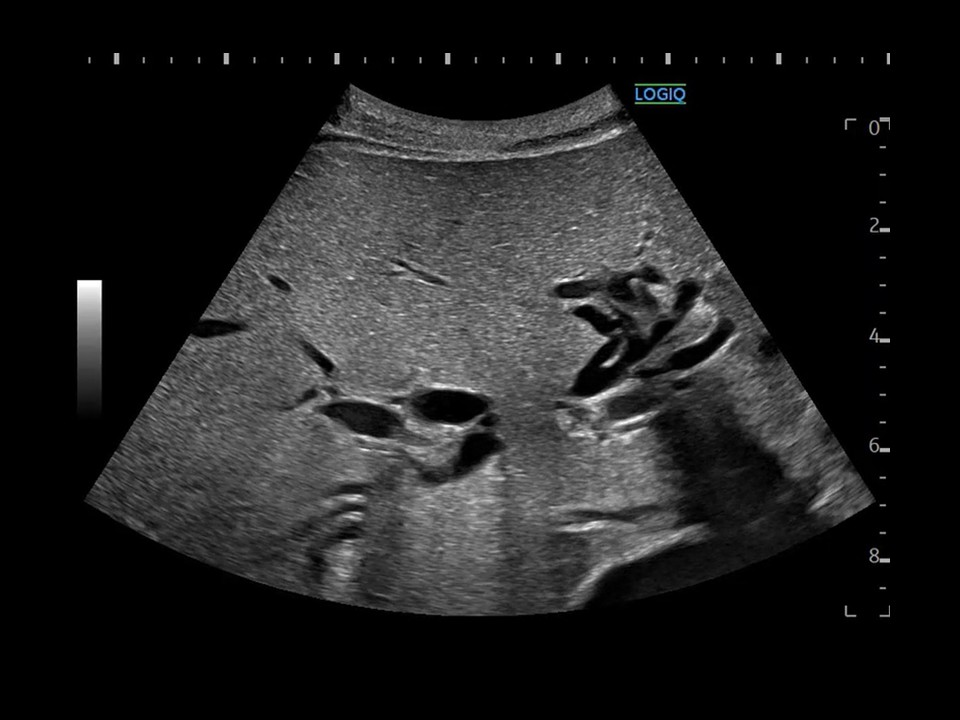

特別賞

本間 めぐみ 日本大学病院

診断名肝門部領域胆管癌

患者:80歳代 男性

使用機種:

GE HealthCare LOGIQ E10

周波数:6.5MHz

コメント(術者の一言)

肝内胆管の泣き別れを綺麗に描出できました。